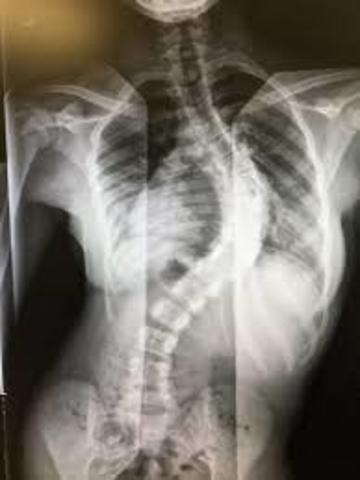

Surgery

I was in fifth grade when I learned I had a condition in my spine called scoliosis. I got back surgery in sixth grade.